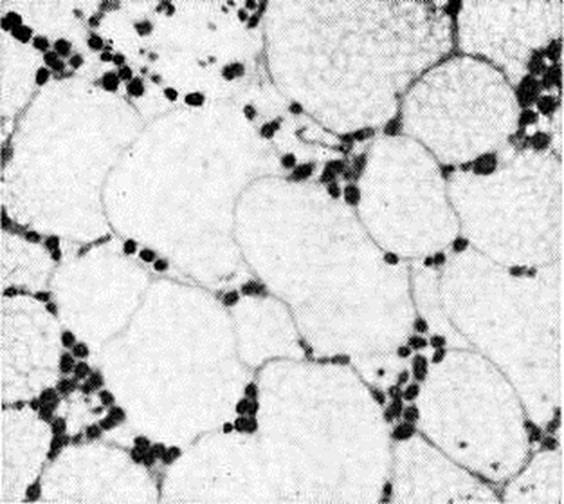

При микроскопическом исследовании костного мозга (смотри полный свод знаний) выявляется различная степень его опустошения. В случае аплазии в жировом костном мозге находят лишь небольшие скопления лимфоцитов, плазматических клеток и недифференцированных элементов, единичных гранулоцитов и нормобластов. При гипоплазии несколько чаще обнаруживают участки кроветворной ткани. Характерна неравномерность распространения очагов кроветворения не только в различных участках скелета, но и в пределах одной и той же кости. Структура костной ткани чаще сохранена. Как для ранних, так и для поздних фаз болезни характерно отложение гемосидерина в селезёнке, печени (рисунок 1) и костном мозге, реже в почках (рисунок 2), лимфатических, узлах. К частым осложнениям Гипопластическая анемия относят фибринозно-геморрагические пневмонии и некротические изменения в слизистых оболочках и серозных покровах, коже, внутренних органах. Течение и симптомы. Заболевание может протекать остро, подостро или хронически. В острых случаях процесс начинается с бурного геморрагического диатеза (смотри полный свод знаний Геморрагические диатезы), тяжёлой общей интоксикации, инфекционных осложнений. Чаще наблюдается постепенное нарастание симптомов. Появляются адинамия, слабость, головокружение, быстрая утомляемость, одышка при физ. нагрузке, иногда боли в костях и области сердца. Отмечается восковидная бледность кожи без желтушности, малокровие видимых слизистых оболочек. Подкожная жировая клетчатка сохранена. При развитии глубокой тромбоцитогонении (смотри полный свод знаний) возникают кровоизлияния на коже, слизистых оболочках и глазном дне, носовые, десневые, маточные, кишечные, почечные и другие кровотечения. При прогрессировании процесса может иметь место неврологический симптоматика, обусловленная геморрагиями в головной мозг. При парциальной Гипопластическая анемия кровоточивость отсутствует. Размеры лимф, узлов, селезёнки и печени не изменяются. Картина крови. Анемия носит нормохромный, нормоцитарный, реже макроцитарный характер. Полихроматофилия отсутствует, число ретикулоцитов нормально или снижено. Лейкопения может достигать 1000 клеток в 1 микролитров. и менее; она обусловлена в основном гранулоцитопенией и сопровождается относительным лимфоцитозом. Абсолютное число лимфоцитов при резкой лейкопении также снижено. Отмечается тромбоцитопения с удлинением времени кровотечения (смотри полный свод знаний) и снижением ретракции кровяного сгустка (смотри полный свод знаний Ретракция). Плазменные факторы свёртывания крови (смотри полный свод знаний Свёртывающая система крови) не изменяются. Содержание сывороточного железа повышено, общая железо-связывающая способность сыворотки чаще повышена. Парциальная Гипопластическая анемия характеризуется хронический нормоцитарной анемией, часто без лейко- и тромбоцитопении, с глубокой ретикулоцитопенией. Пунктат костного мозга, как правило, скудный, ядерные элементы представлены в основном лимфоцитами, немногочисленными гранулоцитами и нормобластами. Мегакариоциты чаще отсутствуют. Иногда, несмотря на явную панцитопению, пунктат оказывается довольно богатым; это связано с попаданием иглы в очаг сохранившегося кроветворения. Помимо чисто количественного дефицита эритробластических элементов, при Гипопластическая анемия отмечают признаки качественной их патологии (дизэритропоэз), мегалобластоидность, атипичные митозы, многоядерность (смотри полный свод знаний Дизэритропоэтическая анемия). При парциальной Гипопластическая анемия пунктат костного мозга богат ядерными элементами, лейкотромбоцитопоэз не нарушен, но число клеток красного ряда нередко резко уменьшено или они полностью отсутствуют. Трепанобиопсия подвздошной кости выявляет резкое преобладание жирового костного мозга над кроветворным (рисунок 3), иногда отсутствие последнего. Исследование с радиоактивным железом 59Fe даёт наиболее точную суммарную оценку эритропоэза: клиренс изотопа из плазмы замедлен, он накапливается в основном в печени, включение метки в эритроциты резко замедлено. Осложнения. Основными осложнениями и непосредственной причиной смерти больных являются кровотечения и инфекционно-воспалительные процессы. Геморрагии выявляются при снижении числа тромбоцитов ниже критического уровня (20 000—30 000 в 1 микролитров.), могут провоцироваться даже незначительными травмами (подкожные инъекции и так далее). Инфекции (пневмонии и другие) развиваются при достаточно длительном и выраженном (менее 500 в 1 микролитров.) снижении числа нейтрофилов. Всякая лихорадка у больных Гипопластическая анемия, как правило, связана с наличием инфекционного очага; описано немало случаев развития у них острого лейкоза. Лейкозы на фоне гипоплазии лучевого или бензольного происхождения относятся к группе миелобластных или миеломонобластных и являются, видимо, поздним результатом лейкемогенного действия фактора, вызвавшего анемию. Значительно реже наблюдается присоединение к Гипопластическая анемия пароксизмальной ночной гемоглобинурии, хотя некоторые авторы трактуют в этих случаях Гипопластическая анемия как гипопластическую стадию данной формы гемолитической анемии. Диагноз основывается на наличии панцитопении и бедного ядерными клетками пунктата или трепаната костного мозга при отсутствии увеличения лимф, узлов, селезёнки и печени. Гипопластическая анемия следует дифференцировать главным образом с панцитопениями другого происхождения. Обнаружение в крови молодых клеток белого или красного ряда, даже незначительное увеличение селезёнки всегда должны вызывать сомнение в диагнозе Гипопластическая анемия. В этих случаях можно предположить наличие алейкемических форм лейкозов (смотри полный свод знаний), раковых метастазов в костный мозг, миеломной болезни (смотри полный свод знаний). Диагноз обычно ставят на основании исследования пунктата костного мозга; миеломной болезни, кроме того, присущи характерные изменения белков сыворотки и (или) мочи. Панцитопения при миелофиброзе (смотри полный свод знаний Остеомиелофиброз) сопровождается, в отличие от Гипопластическая анемия, увеличением и миелоидной метаплазией селезёнки. Анемию Аддисона — Бирмера (смотри полный свод знаний Пернициозная анемия) отличает от Гипопластическая анемия наличие глоссита, неврологический нарушений, ахлоргидрии, выраженного мегалобластоза костного мозга, хорошего терапевтического эффекта от витамина В12. Диагноз пароксизмальной ночной гемоглобинурии даже в её ранней, гипопластической, стадии подтверждается положительными результатами сахарозной и кислотной проб (смотри полный свод знаний Гемолитическая анемия). При подостром варианте лимфогранулематоза (смотри полный свод знаний) панцитопения сопровождается лихорадкой, нет резкого лимфоцитоза, в трепанате костного мозга иногда удаётся обнаружить клетки Березовского — Штернберга. Панцитопения вследствие гиперспленизма сопровождается, как правило, увеличением селезёнки. ЛечениеМетодов радикального излечения Гипопластическая анемия не существует, однако лечебный мероприятия способствуют удлинению продолжительности жизни больных. При выявлении этиологического фактора необходимо прекратить дальнейшее его воздействие. Для борьбы с анемией показаны трансфузии крови или эритроцитарной массы; эта мера не должна преследовать цель полной нормализации показателей красной крови — достаточно поддержание их на уровне, совместимом с сердечно-сосудистой компенсацией. Число трансфузий должно быть минимальным для уменьшения опасности трансфузионного сидероза (при переливании 450 миллилитров крови в организм вводится 200—250 миллиграмм железа), гепатита и других осложнений. Во избежание изосенсибилизации антигенами лейкоцитов и тромбоцитов целесообразно переливать отмытые эритроциты. При многократных гемотрансфузиях нередко развитие изосенсибилизации антигенами эритроцитов; в этих случаях кровь для трансфузии подбирают по непрямой пробе Кумбса (смотри полный свод знаний Кумбса реакция). В случае сочетания анемии с геморрагическим диатезом показаны переливания свежецитратной крови или прямые гемотрансфузии в разовой дозе не менее 500 миллилитров. Более выраженным гемостатическим эффектом обладают тромбоцитарные концентраты, получаемые с помощью сепаратора клеток крови от одного донора или путём центрифугирования большого числа доз крови, взятых от различных доноров. Кровоостанавливающее действие тромбоконцентратов проявляется в том случае, если число тромбоцитов у больного удаётся повысить хотя бы до 15 000 —20 000 в 1 микролитров. крови. При многократных переливаниях тромбоцитарных концентратов, особенно полученных из крови разных доноров, неизбежно развивается изосенсибилизация к тромбоцитарным антигенам и отмечается снижение терапевтической эффективности трансфузий. Поэтому желательно в качестве доноров использовать ограниченное число лиц, лучше родственников, максимально совместимых по антигенам системы HL — А (смотри полный свод знаний Группы крови, лейкоцитарные антигены). Среди лекарственных препаратов свойством стимулировать эритропоэз обладают лишь анаболические стероиды (смотри полный свод знаний). Необходимым условием достижения терапевтического эффекта считают длительность применения гормонов в достаточно высокой дозе (например, метилтестостерон или неробол по 1 — 2 миллиграмм на 1 килограмм веса тела в день внутрь в течение 3—4 месяцев) [Мак-Креди (К. В. Mc-Credie), 1969]. Первым проявлением лечебный эффективности препаратов может быть улучшение показателей периферической крови. При появлении признаков побочного действия (задержка жидкости, поражение печени) гормоны отменяют. Для лечения Гипопластическая анемия применяют также кортикостероиды (преднизолон 0,5—1,0 миллиграмм на 1 килограмм веса тела или эквивалентные дозы других стероидов) главным образом с целью гемостатического действия (понижение сосудистой проницаемости); для этого используют и другие, так называемый сосудоукрепляющие средства — аскорбиновую кислоту, рутин, препараты кальция. С целью уменьшения гемосидероза органов и тканей можно назначать препараты типа десферала. Многочисленные попытки пересадки больным донорского костного мозга, предпринимавшиеся без должного иммунологический подбора (только по основным эритроцитарным антигенам), оказались безуспешными, то есть завершились отторжением трансплантата вследствие биол. несовместимости. Случаи подлинной трансплантации немногочисленны. Томас (Е. D. Thomas) с сотрудники (1974) осуществили у четырёх больных Гипопластическая анемия успешную пересадку сингенного костного мозга, полученного от однояйцевых близнецов больных, приведшую к полному выздоровлению; операция проводилась без специальной подготовки ввиду антигенной идентичности реципиентов и доноров. Однако подобная возможность является казуистической. Аллогенные пересадки (от доноров, совместимых по системе Н1—А) требуют сложной подготовки реципиентов для предотвращения отторжения трансплантата (общее облучение или введение циклофосфана с целью иммунодепрессии), а также послеоперационного применения цитостатиков для подавления иммунологический реакции «трансплантат против хозяина» (смотри полный свод знаний Несовместимость иммунологическая). Из 24 больных Гипопластическая анемия, описанных Томасом с сотрудники, 12 прожили свыше 3 месяцев; приживление у них трансплантата было доказано в результате анализа полового хроматина (смотри полный свод знаний). У больных, получивших ранее многочисленные гемотрансфузии, шансы на приживление трансплантата в связи с образованием изоантител снижаются. Сложность методики пересадки костного мозга делает ее доступной лишь для отдельных специализированных учреждений. Вопрос об эффективности спленэктомии окончательно не решён. При выраженных геморрагиях операция противопоказана в связи с высокой летальностью. Вероятно, более целесообразна спленэктомия (смотри полный свод знаний) у больных с повышенной секвестрацией тромбоцитов и эритроцитов в селезёнке, доказанной радиоизотопным методом, и при сохранности очагов нормального кроветворения в костном мозге. ПрогнозПрогностически неблагоприятным признаком считают острое начало болезни. Формы с острым течением обычно устойчивы к терапии и через несколько недель заканчиваются смертью. Чаще течение болезни затяжное, многомесячное и даже многолетнее. Возможно длительное отсутствие клин, проявлений заболевания, однако у больных сохраняются признаки неполноценного костномозгового кроветворения. ПрофилактикаЛица, профессионально связанные с воздействием миелотоксических факторов (источники ионизирующей радиации, бензольное производство), должны находиться под постоянным диспансерным наблюдением. Проведение цитостатического лечения по поводу опухолей и других заболеваний требует регулярного контроля состава крови и своевременного прекращения при угрозе гипоплазии кроветворения. Применение потенциально опасных препаратов, в первую очередь левомицетина (смотри полный свод знаний), должно быть ограничено прямыми показаниями и находиться под контролем состава крови. Профилактика геморрагий при уже развившейся Гипопластическая анемия включает гормональное подавление менструального цикла у женщин с массивными меноррагиями, замену (по возможности) инъекционных лечебный препаратов пероральными, щажение слизистых оболочек (исключение грубой пищи, замена жёстких зубных щёток ватными тампонами). Для предотвращения инфекционных осложнений при глубокой гранулоцитопении (смотри полный свод знаний Лейкопения) рекомендуется подавление кишечной аутофлоры неабсорбируемыми антибиотиками, больных следует содержать в асептических или близких к ним условиях, следить за соблюдением личной гигиены. Гипопластическая анемия у детей. Приобретённые формы Гипопластическая анемия у детей протекают так же, как у взрослых. Наряду с ними в детском возрасте встречаются и некоторые врождённые (конституциональные) формы болезни. Анемия Фанкони (синонимы: синдром Фанкони, врождённая панцитопения). Описана в 1927 год под названием «семейная детская пернициозоподобная анемия». С тех пор опубликовано около 200 наблюдений. Анемия, как правило, выявляется в первые годы жизни, изредка позже. Мальчики болеют в 2 раза чаще девочек. Характерно сочетание панцитопении и гипоплазии костного мозга с другими врождёнными дефектами — коричневой пигментацией кожи в связи с отложением меланина, атрофией почек и селезёнки, отсутствием или недоразвитием 1 пястной или лучевой костей, задержкой умственного, физ. и полового развития, микроцефалией, микроофтальмией. При культивировании лимфоцитов и фибробластов кожи больных выявляются многочисленные хромосомные аберрации. У родственников больных часто отмечают лейкозы. Лечение — назначают систематические переливания крови (эритроцитарной массы). Прогноз неблагоприятный. Семейная гипопластическая анемия Эстрена — Дамешека впервые была описана в 1947 год. Ей свойственны те же изменения со стороны кроветворения, которые наблюдаются при анемии Фанкони, но аномалий развития скелета и внутренних органов не наблюдается. Врождённая парциальная гипопластическая анемия Джозефса — Даймонда — Блекфена описана в 1936 год Джозефсом (W. Н. Josephs) и в 1938 год Даймондом и Блекфеном (L. К. Diamond, К. D. Blackfan). Генетический дефект, лежащий в основе болезни, не выяснен. Развитие болезни у нескольких детей, родившихся от разных матерей, но от одного отца, свидетельствует о доминантном характере наследования. Развёрнутая картина болезни обычно обнаруживается уже на 1-м году жизни: анемия различной степени сочетается с глубокой эритро- и нормобластопенией на фоне уменьшения количества миелокариоцитов (на начальных этапах развития болезни количество миелокариоцитов костного мозга может быть не изменено). У части больных выявляют другие врождённые дефекты (задержка полового и физических развития), но аномалии развития почек не встречаются. Вследствие многократных гемотрансфузий нередко развивается гемосидероз с портальным циррозом печени (смотри полный свод знаний Циррозы печени). Лечение — систематические переливания крови (эритроцитарной массы) в сочетании с кортикостероидными гормонами и витамином В12. При помощи систематических гемотрансфузий удавалось довести больных детей до 8—15 лет, после чего наступало спонтанное улучшение. Смотри также Анемия.